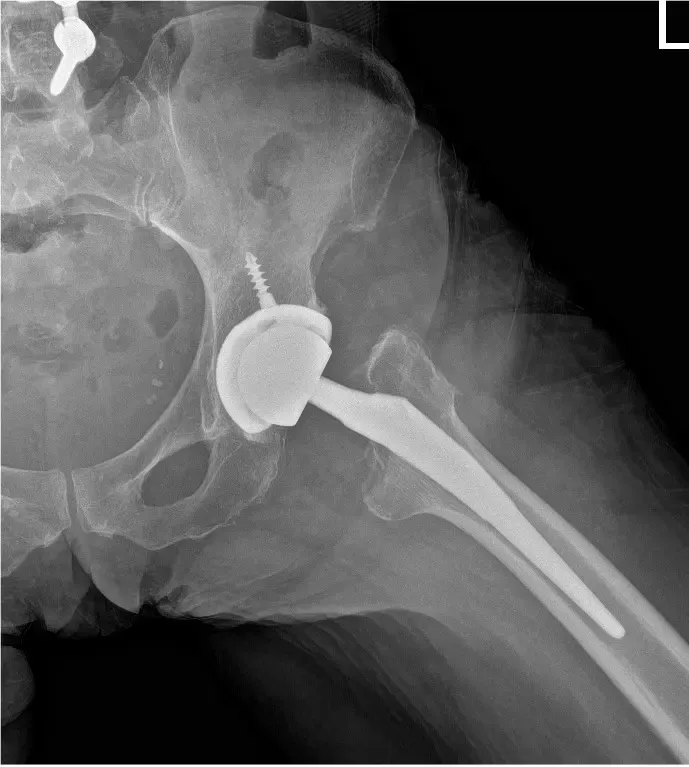

The remainder of the labrum was then removed. The acetabulum was sequentially reamed. The final shell was then placed into position in the correct abduction and anteversion. A screw was used for additional stability. A poly was placed over the shell. Attention was then turned towards the femur. The contralateral extremity was placed over a Mayo stand and the left lower extremity was placed in a figure of 4 position. The canal was sequentially broached.

The final broach was left into position. The trunnion and the head were placed over the broach. The hip was then reduced trialed through a full range of physiological motion and the hip was stable in all physiological range of motion. Fluoroscopy was obtained to ensure the correct length. Hip was dislocated. The trial components were then removed. Final components were then placed into position and the hip was then reduced. Thorough lavage was given. The wound was then closed in layers.

Similarly on the right hand side, a curvilinear incision was made. The patient was found to be stable to undergo a second hip replacement. The anterior approach was developed over to the right hip, though head of the femur was exposed in situ resection was made. The head was then removed. The acetabulum was then exposed. The labrum was then debrided. The acetabulum was sequentially reamed and the final shell was then placed into position in the correct abduction and anteversion.

A screw was used for additional fixation. The poly was then placed over the shell. The femur was then exposed after placing the contralateral extremity over the mayo stand and a figure of 4 position was used to broach the canal. Final broach was left into position. The head and trunnion were then placed over the broach and the hip was reduced. The hip was then trialed through a full range of physiological motion and the hip was stable through all physiological range of motion.

Fluoroscopy was carried out to ensure that both the limb lengths were equal. The trial components were then removed and the final components were placed into position and the hip was then reduced. Thorough lavage was given. The hip was then closed in layers. The patient was then transferred to the postoperative care unit in stable condition.